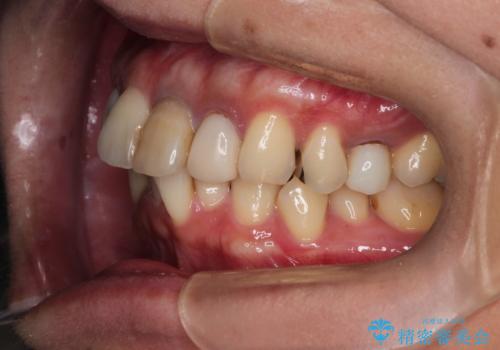

- 全体的なガタガタと前歯をきれいにしたいとのことで来院されました。

下の歯は重度のガタガタがあり、上の前歯は何本かが神経の治療がしてある状態でした。

インビザラインにて歯並びを整え、上顎の前歯にセラミックを装着する計画としました。